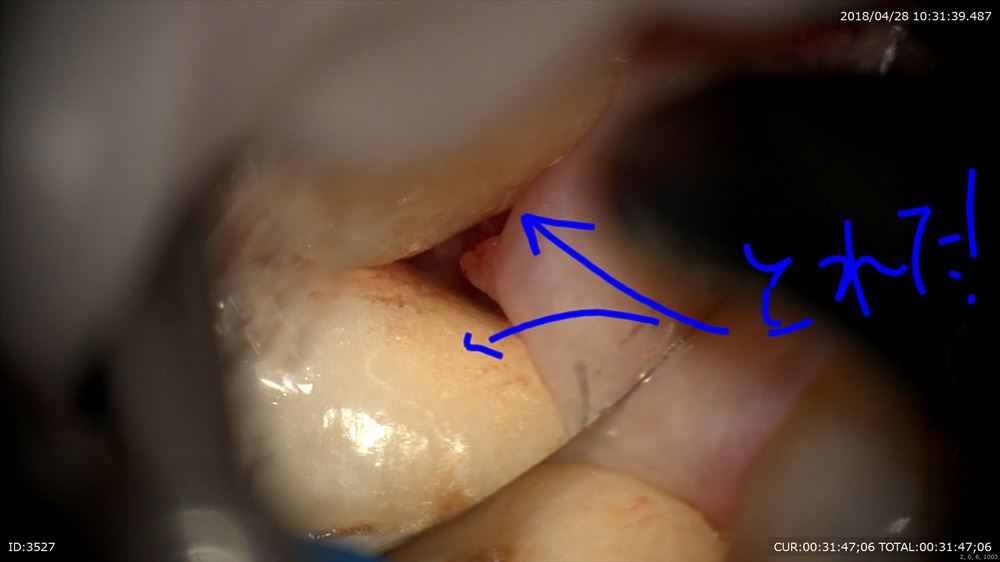

こんにちは。今日は歯周病患者さまの無痛デブライドメントを行いました。マイクロスコープで行うとこんな風に見えます。

歯石の付きやすい(歯周ポケットの出来やすい部位)所。臼歯部遠心隅角。

はっきり見えますよね。

手指の感覚で、、、、、なんて必要ありません。

ここは6mmのポケット。必ずほら「歯石(細菌)」が付着。

で見て取れば

誰でも取れます。